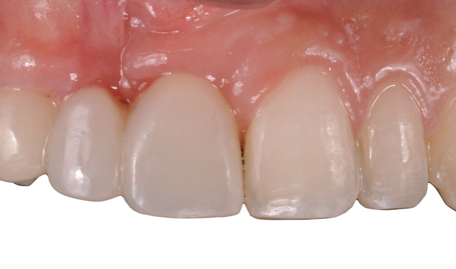

After the 3rd bone graft failed, the patient sought second opinions. She was a college sophomore at the time. Using a combination of interdisciplinary therapies, including S.M.A.R.T. minimally invasive bone grafting, Dr. Ernesto Lee was able to tridimensionally reconstruct this severe defect and place implants to restore the patient’s smile. The S.M.A.R.T. bone graft was also extended to treat adjacent teeth with thin/dehisced bone.

A long-term CAD/CAM fabricated temporary restoration is in place while she finishes medical school at an out-of-state university. The treatment of this case was published in detail in a special issue of the Compendium of Continuing Education in Dentistry, one of the largest circulation journals in our profession.